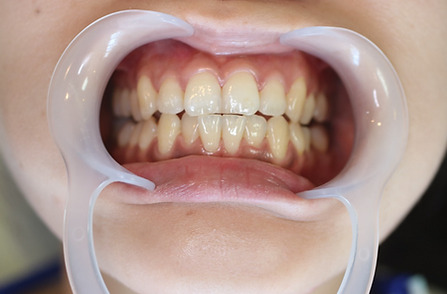

2ホワイトニング【治療例1】

治療前

治療後